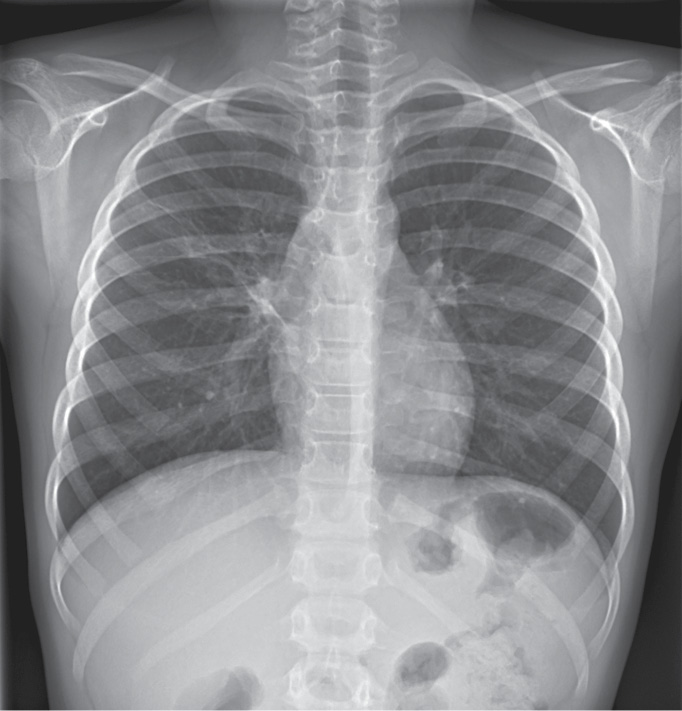

15.05 на рентгенограмме ОГК отмечено уменьшение распространенности и интенсивности инфильтрации в S2–S3 справа; объем S3 справа уменьшен за счет ателектатического компонента; корень правого легкого расширен, уплотнен; легочный рисунок усилен за счет интерстициального компонента в прикорневых отделах с обеих сторон; горизонтальная междолевая плевра подчеркнута и подтянута кверху; тень сердца размыта в верхних отделах справа; контуры диафрагмы четкие, ровные; плевральные синусы свободны (рис. 2). Аускультативно в легких единичные влажные хрипы при форсированном дыхании.

Рис. 2. Рентгенограмма ребенка Н., 8 лет 7 мес., 15.05

Fig. 2. X-ray of the child N., 8 years 7 months, 15.05